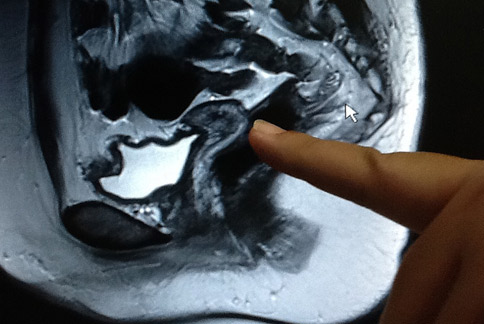

博元試管嬰兒成功案例分析 :如何打排卵針,影響試管嬰兒成功率! (案例一) :這一對不孕症夫妻 ,已經不孕症長達 7年 .做過一連串的檢查跟治療 ,包括 4次人工授精及 7次試管嬰兒 ,都沒沒有成功 .前 7次試管嬰兒取卵數...